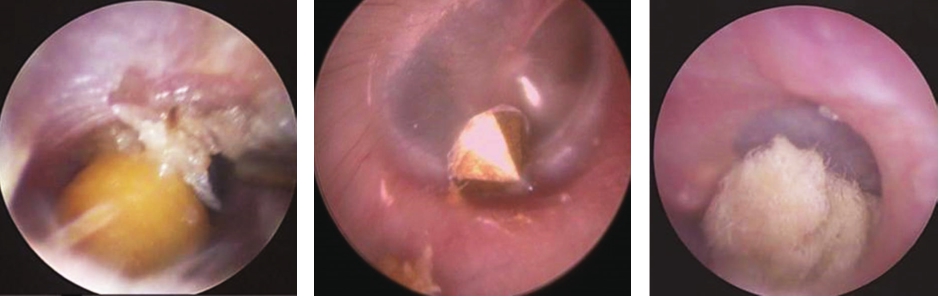

2.有孔异物可用钩针取出(图5-3),必要时可以拨动异物,调整角度后将钩针钩入孔中取出。

图5-3 有孔异物可用钩针